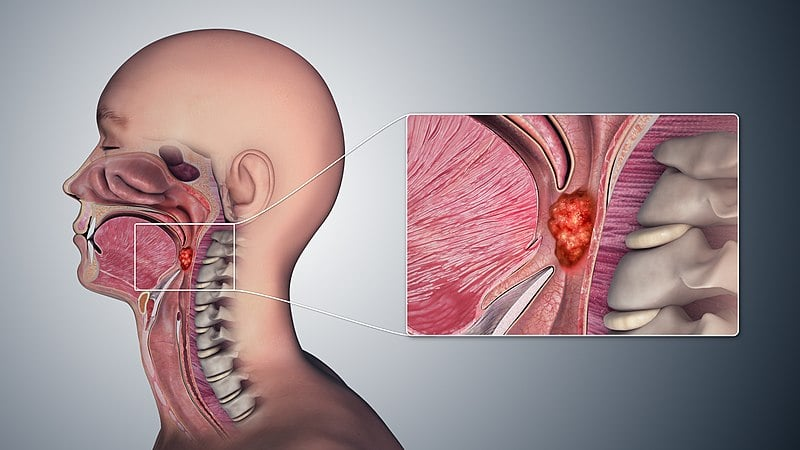

O câncer de orofaringe, como é chamado, pode se desenvolver em áreas como amígdalas, base da língua e parte posterior da garganta. Segundo especialistas, além dos fatores genéticos e exposição ao HPV, algumas práticas comuns entre mulheres têm sido associadas ao aumento dos casos.

Entre os principais fatores, estão o tabagismo, o consumo frequente de álcool e o sexo oral desprotegido, especialmente com múltiplos parceiros. Essas práticas, quando mantidas ao longo dos anos, podem favorecer infecções que resultam em alterações celulares e no surgimento de tumores.

O HPV, por exemplo, já é reconhecido como um dos principais causadores do câncer de colo do útero e também está diretamente relacionado ao câncer de garganta.

Mulheres que mantêm relações orais sem proteção com parceiros infectados pelo HPV estão em risco, mesmo que o vírus não apresente sintomas visíveis no parceiro. O vírus pode se alojar na mucosa da garganta e, com o tempo, provocar alterações celulares que resultam em tumores.

Além disso, o uso frequente de cigarro e álcool potencializa o risco. Essas substâncias causam irritações constantes na mucosa da garganta, criando um ambiente propício para a ação de vírus e mutações celulares. Quando combinadas, essas práticas elevam ainda mais as chances do desenvolvimento de tumores malignos, especialmente em mulheres que não fazem acompanhamento médico regular.